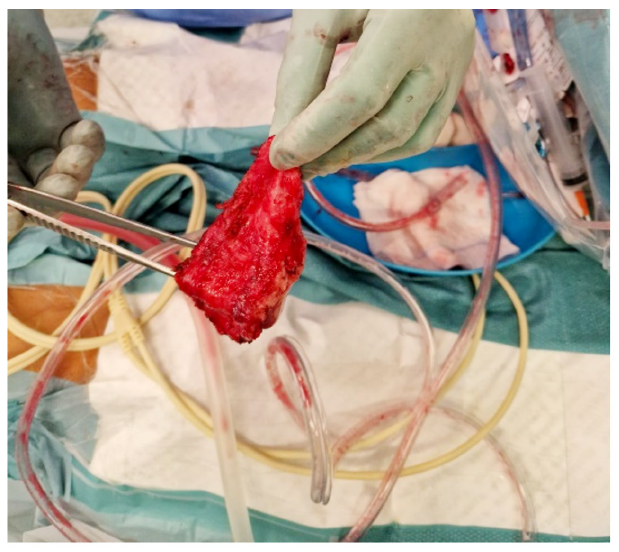

Despite targeted therapy and initial favourable progress (with a reduction in pericardial effusion seen in serial echocardiograms), on the 28th day of hospitalization, the patient developed pleuritic chest pain without relieving factors, accompanied by tachycardia and predominantly vespertine fever. This prompted repetition of the transthoracic echocardiogram (TTE), which showed a resurgence of pericardial effusion with mild to moderate fibrin deposition, pericardial effusion "swinging heart" type, with maximum expression inferoposteriorly measuring 44 mm (in the apical segment), free wall of the right ventricle measuring 39 mm, retroauricular space measuring 35 mm, and lateral space measuring 22 mm. There was slight partial collapse of the right heart chambers (systolic collapse of the right atrium and diastolic collapse of the right ventricle), with more than 25% reduction in the E wave of the mitral valve during inspiration and more than 40% reduction in the E wave of the tricuspid valve during expiration, indicating ventricular interdependence. Considering these TTE findings, an urgent pericardiocentesis was performed for diagnostic and evacuative purposes, yielding 1.150 mL of serosanguinous fluid, characterized as an exudate. The patient was started on antituberculosis therapy as well as slight compromise of overall systolic function, associated with ventricular interdependence and paradoxical movement of the interventricular septum. Given findings consistent with effusive-constrictive pericarditis, a cardiac Magnetic Resonance Imaging (MRI) was requested. The MRI revealed a non-dilated right ventricle (telediastolic volume (EDV) 79 mL, 52 mL/m2; telesystolic volume (ESV) 37 mL, 24 mL/m2; stroke volume (SV) 27 mL/m2), with preserved systolic function (ejection fraction 53%), pericardial thickening (15 mm) (Fig.1, panel A), and suggestive calcification adjacent to the right ventricle wall. Real-time imaging demonstrated septal deviation towards the right ventricle during inspiration, consistent with constrictive physiology (Fig. 1, panel C). With the diagnosis of acute constrictive pericarditis, the patient was proposed for partial pericardiectomy, (Fig. 2). At the time of discharge, he had preserved systolic function. He was reevaluated one month after the procedure, with cardiac MRI showing no evidence of constrictive physiology.